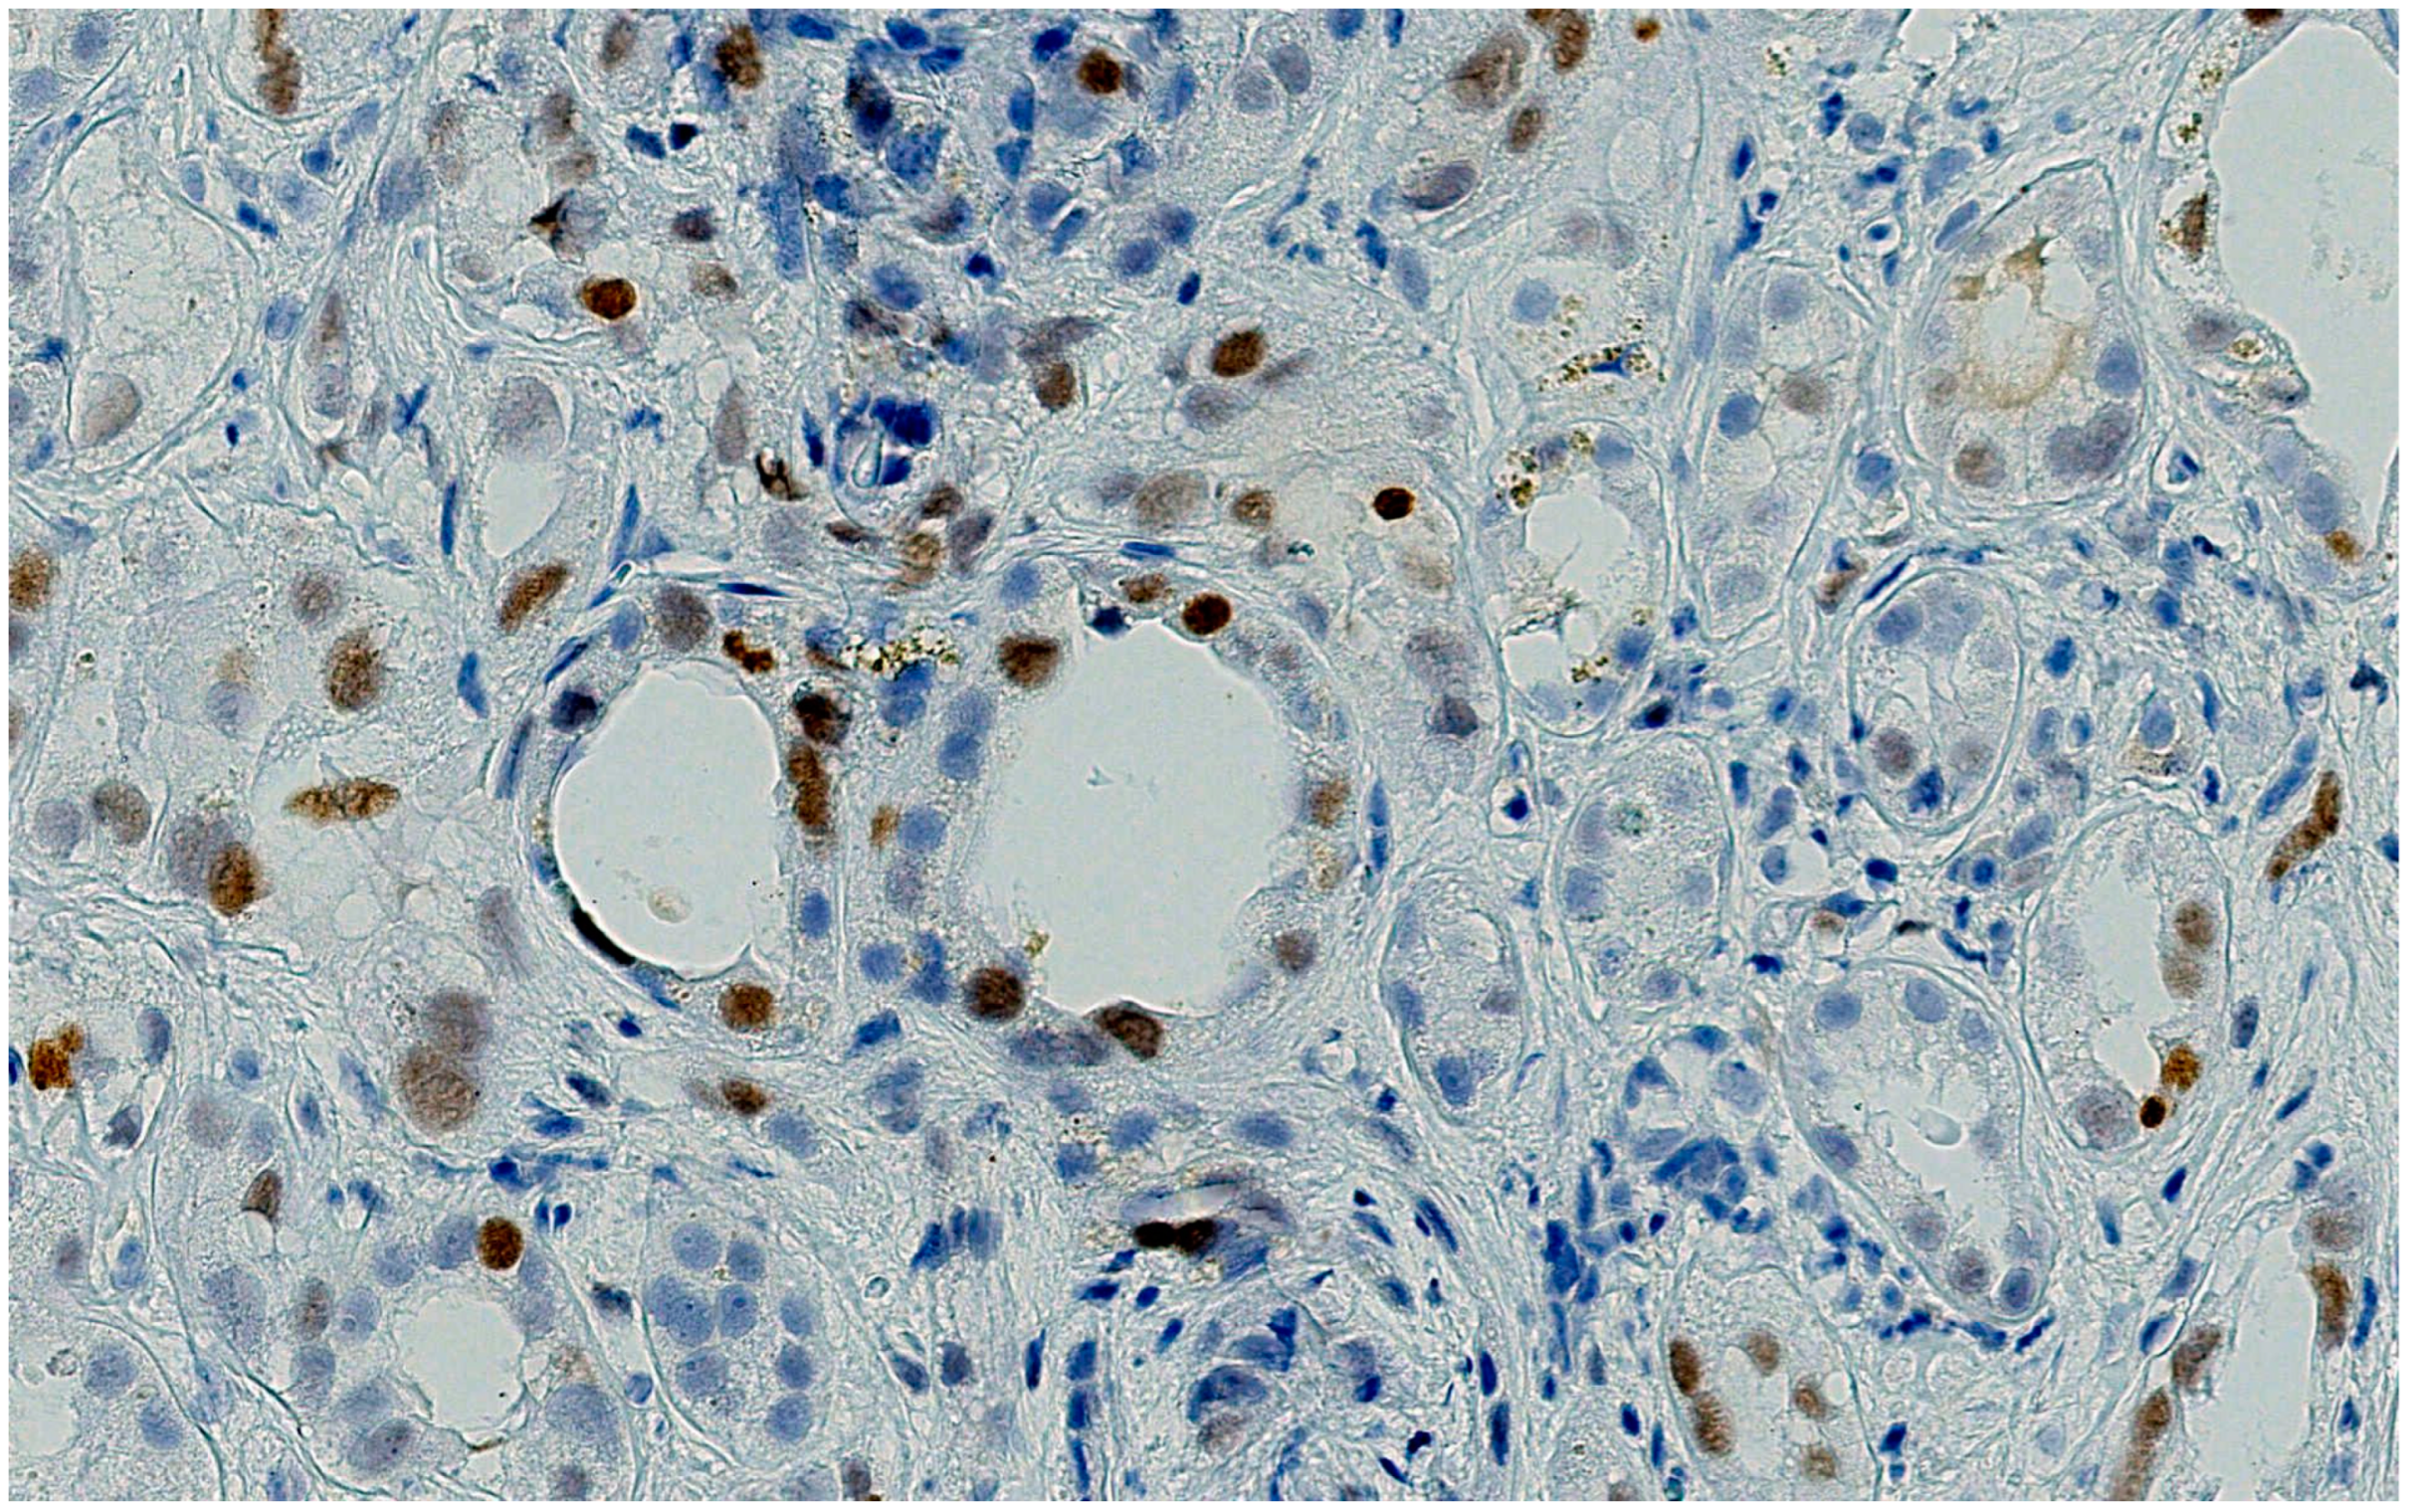

The patient developed nephrotoxicity after the second cycle, for which renal biopsy was performed. Renal biopsies showed no glomerular proliferative lesions, and electron microscopy did not reveal any electron-dense deposits. Severe tubular damage, characterized by the loss of the brush border, flattening of the epithelium, vacuolization, and tubular distalization with focal tubular necrosis were present together with signs of tubular regeneration such as cariomegalia and mild atypia. The underlying chronic renal damage was mild to moderate, with interstitial fibrosis and tubular atrophy not exceeding 10%. No significative lymphocyte infiltration was observed, and the immunohistochemical assessment of PDL-1 was negative. It was noteworthy that the antibody anti-p53 showed a patchy moderate-to-strong staining of the nuclei of proximal renal tubules (Figure 1, Figure 2, Figure 3 and Figure 4).

Figure 2.

The same nuclei showed a brisk nuclear immunostaining for P53 (DAB. X200.P53 NEW).

Figure 3.

Weak and focal tubular decoration of PDL-1; the interstitial space appears free of inflammatory infiltrate.

Figure 4.

An example of the pattern of PDL-1 expression in checkpoint inhibitor tubule-interstitial nephritis: A brisk expression, in both inflammatory and tubular epithelium, in correspondence of the inflammatory foci is evident.

A thorough morphological examination including electron microscopy can assist a nephropathologist in distinguishing between ATN and AIN lesions with greater precision. However, both drugs can cause both pathological patterns, making it necessary to use advanced immunohistochemical techniques to determine which drug is responsible for the nephrotoxicity. In our case, the tubular expression of anti-PD1 was negative, while the tubular expression of p53 was positive.